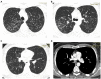

Sarcoidosis is a multisystem granulomatosis of unknown origin, which can involve almost any organ. Most frequently the disease involves the lungs and mediastinal lymph nodes, but it can affect the skin, the eyes, nervous system, the heart, kidneys, joints, muscles, calcium metabolism, and probably any other anecdotical organ involvement. Cardiac sarcoidosis is one of the most challenging involvements, as it can lead to cardiac mortality and morbidity, and also because the diagnosis may be difficult. With no specific symptoms, cardiac sarcoidosis may be difficult to suspect in a patient with no previous extra-cardiac sarcoidosis diagnosis. This manuscript reviews the current knowledge of the diagnosis and decision to treat cardiac sarcoidosis, and illustrates the information with a case presentation of a young adult with no risk factors, no previous diagnosis of sarcoidosis, and with cardiac symptoms impairing his quality of life.